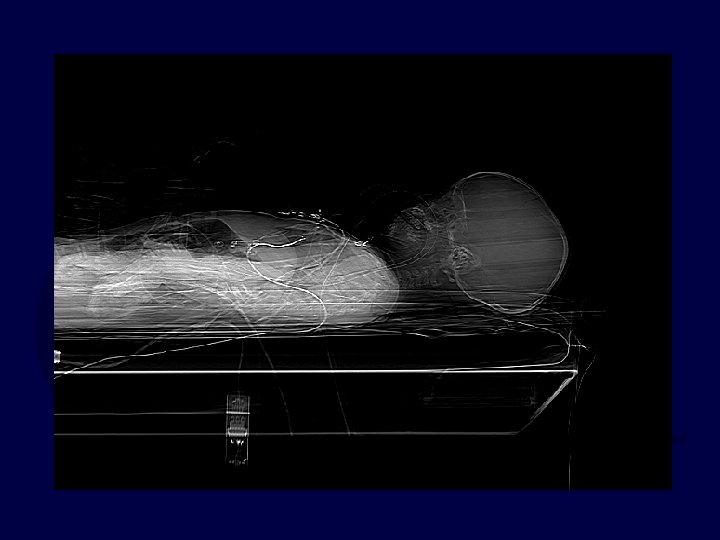

• 11 M, motorcross, flew over handlebars